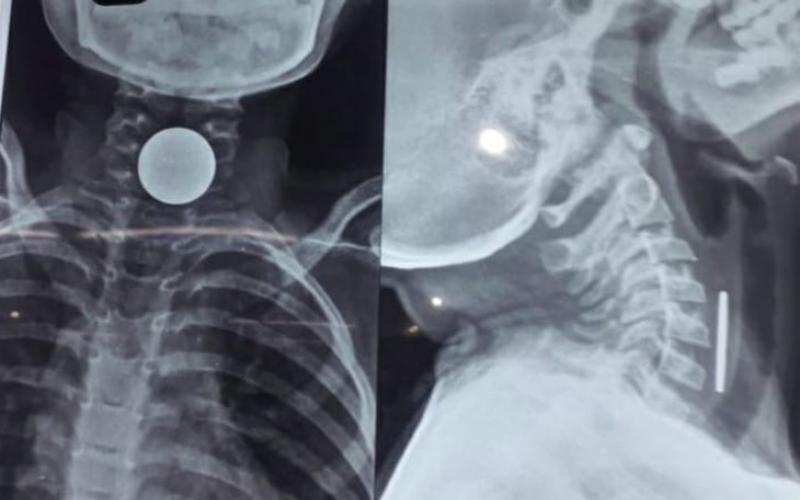

8 साल के मासूम के सीने में सिक्का फसने से मौत

कोरबा (खबरगली) कोरबा जिले में एक 8 साल के मासूम बच्चे के सीने में सिक्का फंसने से उसकी मौत हो गई। शिवम सारथी ने सिक्का कब और कैसे निगला इसकी जानकारी परिजनों को भी नहीं थी। जब तबीयत बिगड़ी तब वे जिला अस्पताल लेकर पहुंचे। जहां एक्सरे रिपोर्ट में सिक्के फंसने की पुष्टि हुई। परिजनों का आरोप है कि कोरबा जिला अस्पताल के डॉक्टरों ने बच्चे की हालात गंभीर बताई और कहा कि इसकी दवा नहीं है यहां इलाज नहीं हो सकता कह दिया। जिसके बाद परिजन बच्चे को निजी अस्पताल ले जा रहे थे।